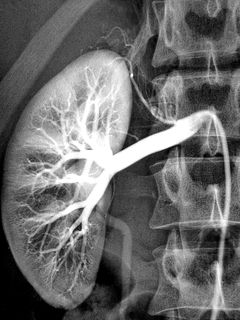

Angiografie je speciální rentgen pro znázornění cév v části organismu po předchozím vstříknutí kontrastní látky.